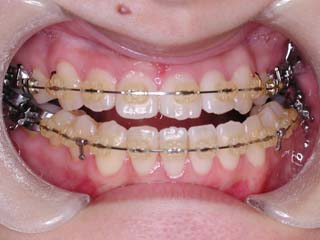

主訴:顎の歪み

診断名:骨格性下顎左方偏位

年齢:24歳

使用した主な装置名:TPB、マルチブラケット装置

抜歯/非抜歯および抜歯部位:非抜歯

治療期間:動的処置1年6か月、経過観察3年

費用の目安:保険適応 自己負担金として30~50万

リスク、副作用:外科手術によるリスク、マルチブラケット治療に伴う歯根吸収など偶発症が発生するリスクがある。

極めて強い側方変位を認めます。前後的・垂直的な問題は見られません。大きなズレであれば、外科的に骨のズレを改善する治療が選択されます。横断的な問題はその他の不正咬合と比較して、解決がかなり難しい事が多いです。治療後の後戻りが頻繁に見られる不正咬合ですので、外科矯正での改善が望ましい場合も多いでしょう。

このケースでは、外科手術は、上顎の傾斜の改善をLeFort1にて、下顎の正中の改善をSSROにて行いました。